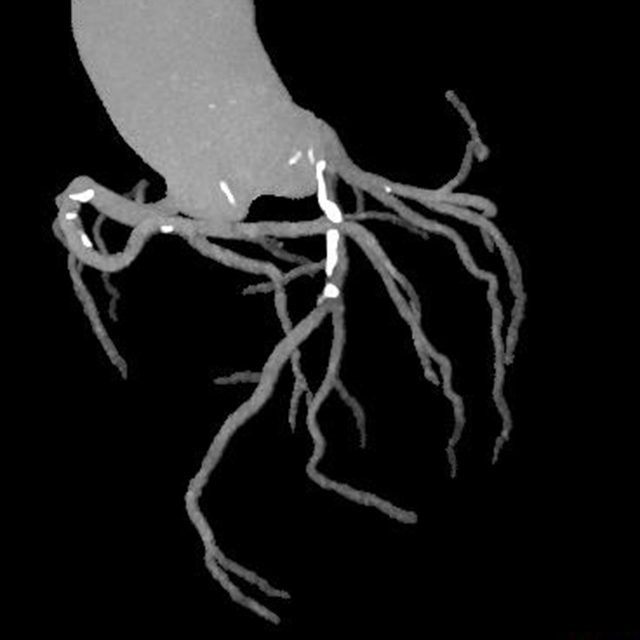

术后检查

这个真实案例强调了胸痛的凶险性、致命性以及一站式CT检查在及时诊断和治疗方面的不可或缺性。

2.主动脉夹层的检测:这一检查能够清楚地显示主动脉的解剖结构,帮助医生观察主动脉夹层并确定其位置和严重程度,及时进行干预。